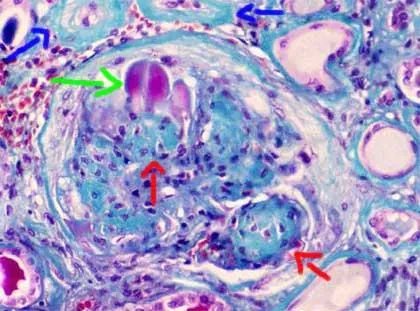

肺部纤维化能活多久与肺部纤维化的具体情况有关,简单的说,对于局限性的肺部纤维化,引起人体症状也比较轻微大多数没有任何症状,更不会影响人的寿命。而特发性肺纤维化,从出现症状到死亡,平均的生存期在2~3年。因此,特发性肺纤维化在整个肺部都呈现为弥漫性的肺纤维化改变,引起肺的通气功能和换气功能障碍,并且呈进行性的发展,不可逆的改变,目前没有特效药,最终因呼吸衰竭而死亡。